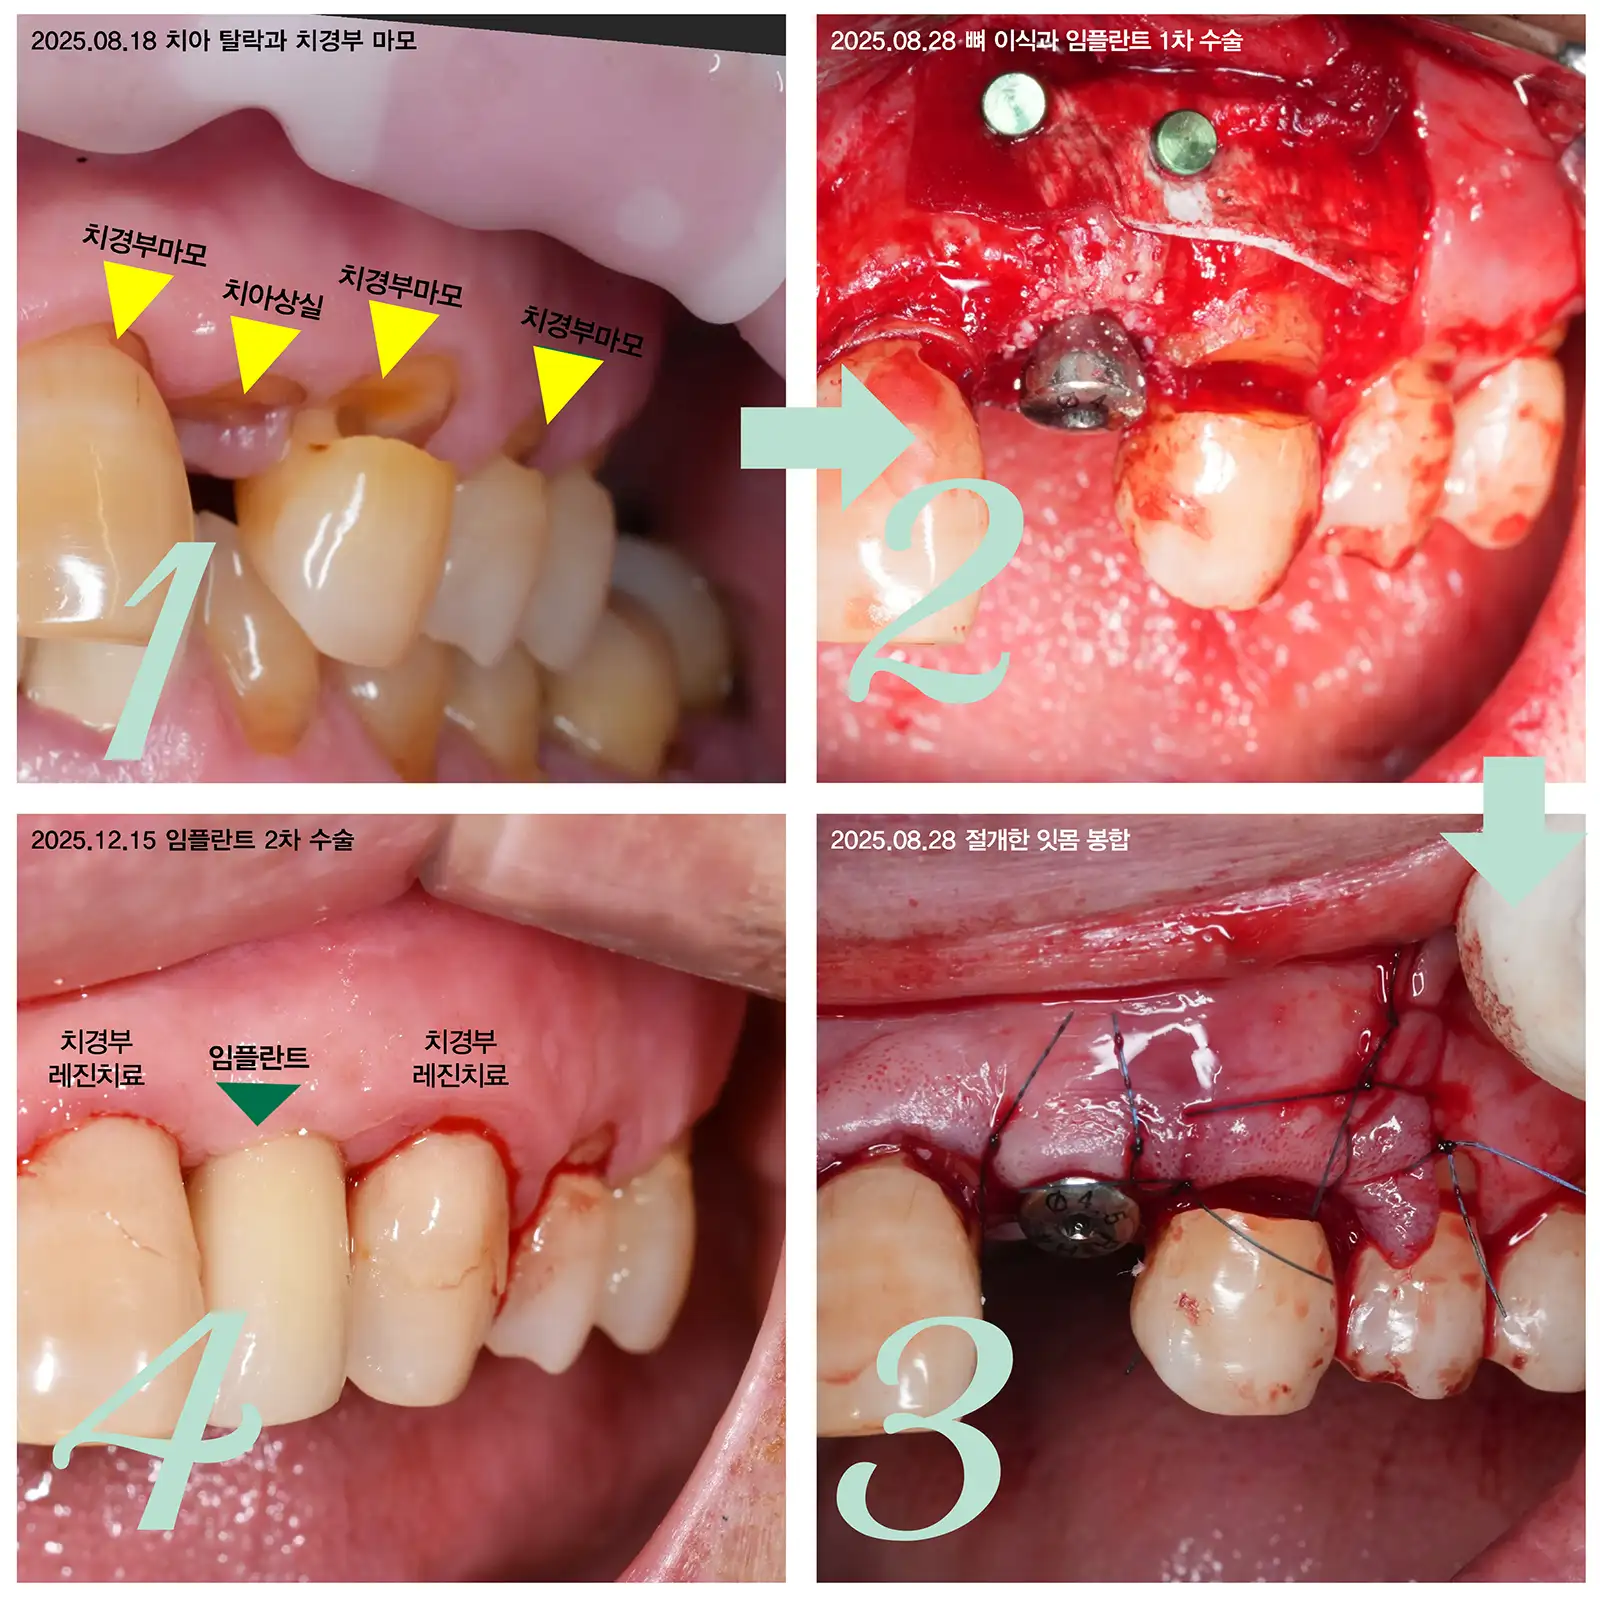

잇몸절개후 뼈이식과 임플란트 수술 사례

임플란트 뼈이식은 잇몸뼈가 녹아 임플란트를 심기 얇은 부위에 인공 뼈를 채워 두께를 만드는 수술입니다.